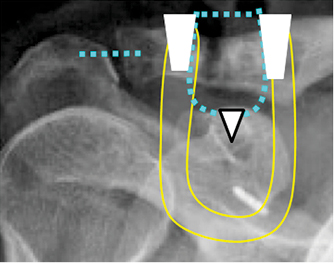

Para elaborar el diagnóstico y el seguimiento se obtuvieron radiografías frente (anteroposterior), axilar y frente caudocefálica de la articulación acromioclavicular. Durante el seguimiento postoperatorio se tomaron radiografías al cumplir el mes, a los 3, 6 y 12 meses. La estabilidad acromioclavicular postoperatoria se evaluó de acuerdo con los criterios de Rosenorm; la articulación AC se considera estable si no hay luxación comparada con la contralateral; subluxada si hay un desplazamiento menor de 50% comparado con la contralateral y luxada si existe un desplazamiento de 100% de la articulación acromioclavicular.

También se evaluaron la estabilidad tanto en plano coronal como axial, osificaciones coracoclaviculares, signos de artrosis acromioclavicular y/o osteólisis distal de clavícula.

A continuación se realizan las suturas correspondientes, comenzando por la AC con Fibertape para dar estabilidad en el plano axial. Luego la sutura sintética coracoclavicular sobre la clavícula a través de los orificios y finalmente se ancla el injerto en los mismos orificios coracoclaviculares para aportar el componente biológico. Éstos proporcionan la estabilidad en el plano coronal obteniendo una reducción anatómica de la articulación acromioclavicular (Figura 3).